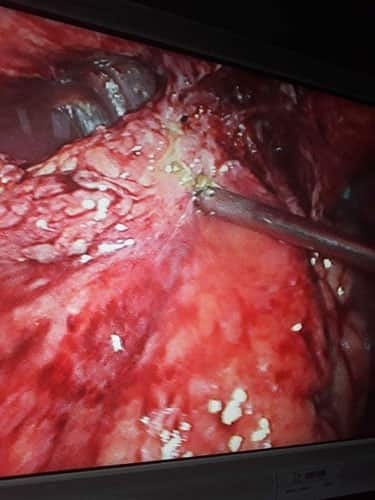

A Young lady who was a small kid...when her mother was operated for a Complex Gastrointestinal condition almost 14 years back by Dr Suddhasattwa Sen suddenly came in with severe blood loss from Gastrointestinal tract with a loss of almost 2 to 3 litres of blood with Shock with fainting . Further stabilisation was done and then extensive investigation revealed not only Piles and GI Ulcers but also SRUS Bleeding ulcers in rectum. A condition called Solitary Rectal Ulcer Syndrome ( a complex and difficult to cure anorectal problem ) . Her hemoglobin dropped to below 7 gm% She finally underwent surgery after 5 days and left home after 2 days post op without any further bleed or problems .